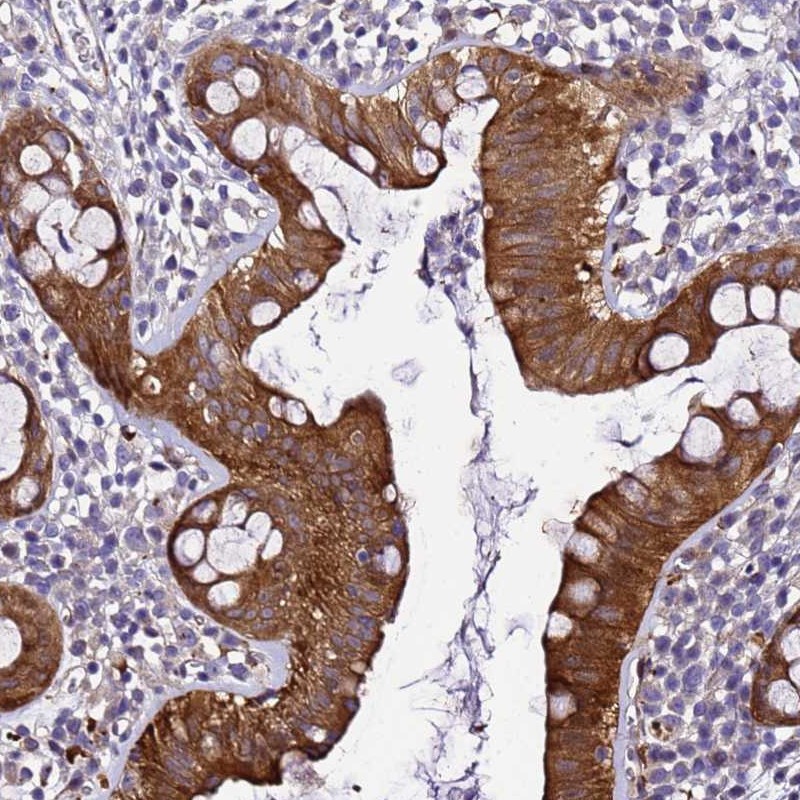

Immunohistochemical staining of human rectum shows strong cytoplasmic positivity in glandular cells.